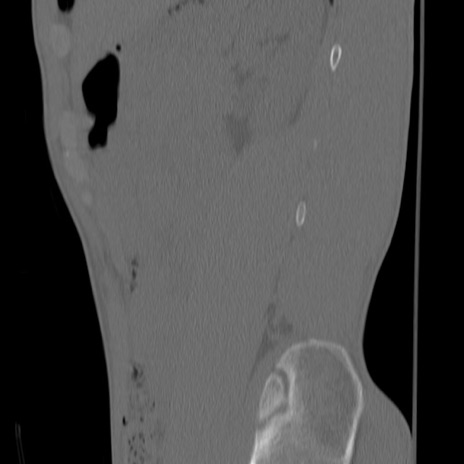

症例3 腰椎CT(矢状断像)

腰椎CT

冠状断像